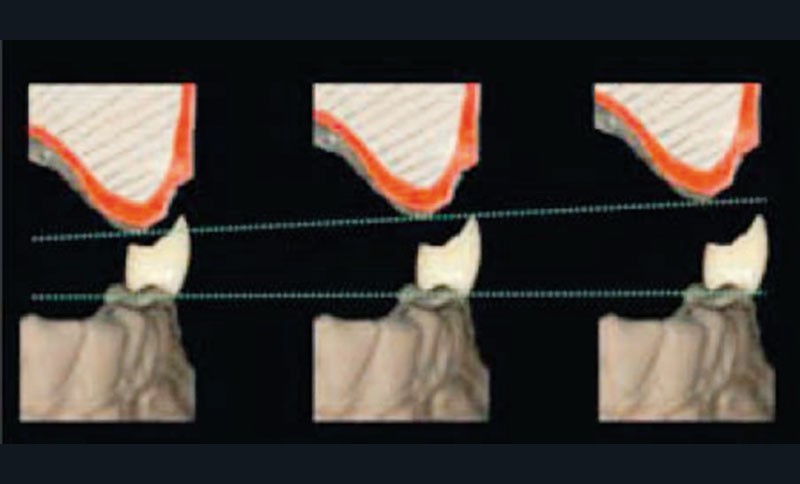

Le choix d’une prothèse amovible complète supra implantaire (PACSI), par opposition à une prothèse fixe implanto-portée, est guidé par différents facteurs. Nous retrouvons en premier lieu le degré de résorption osseuse, le niveau de décalage des bases osseuses, l’espace inter- arcades, la qualité osseuse, le volume osseux disponible, les moyens financiers du patient, et le refus de techniques de chirurgie lourde pour les personnes âgées (fig. 1 et 2).

La prothèse amovible sur implants doit être immédiatement envisagée en cas de résorption modérée à sévère de l’os alvéolaire (4).